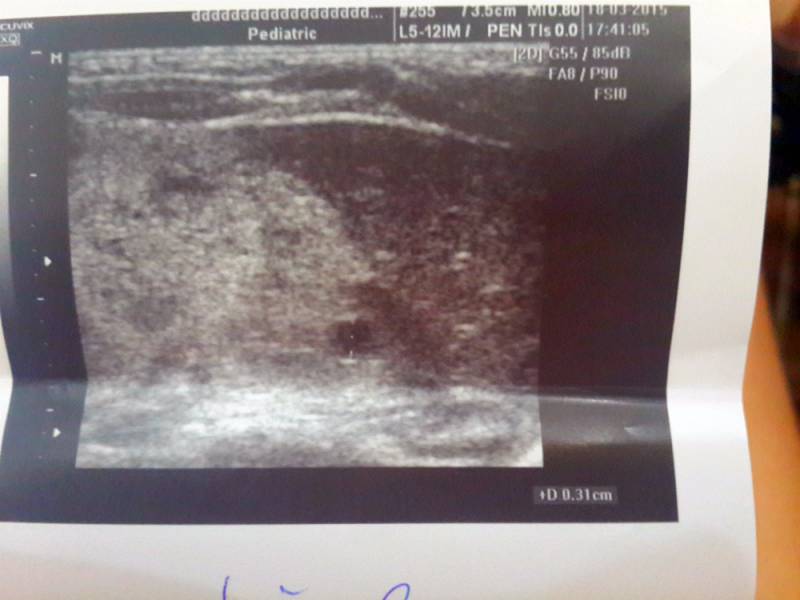

Здраствуйте еще раз!Михаил Юдович посмотрите пожалуйста наши снимки..

Судя по всему - выраженная гиперэхогенность паренхимы почек с единичными кистами без значительного увеличения размеров почек. Я бы назвал это кистозной дисплазией, и , думаю, без возможностей генетического исследования уточнить будет сложно.

А есть ли все-таки возможность что-либо сказать по прикрепленным снимкам?

Цитата Miosotas (  ) А есть ли все-таки возможность что-либо сказать по прикрепленным снимкам? Мне сложно, т.к. сложно оценить степень эхогенности паренхимы, не зная, как был настроен дисплей